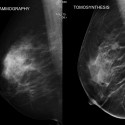

Μαστογραφία

Μαστογραφία

Μαστογραφία και τομοσύνθεση